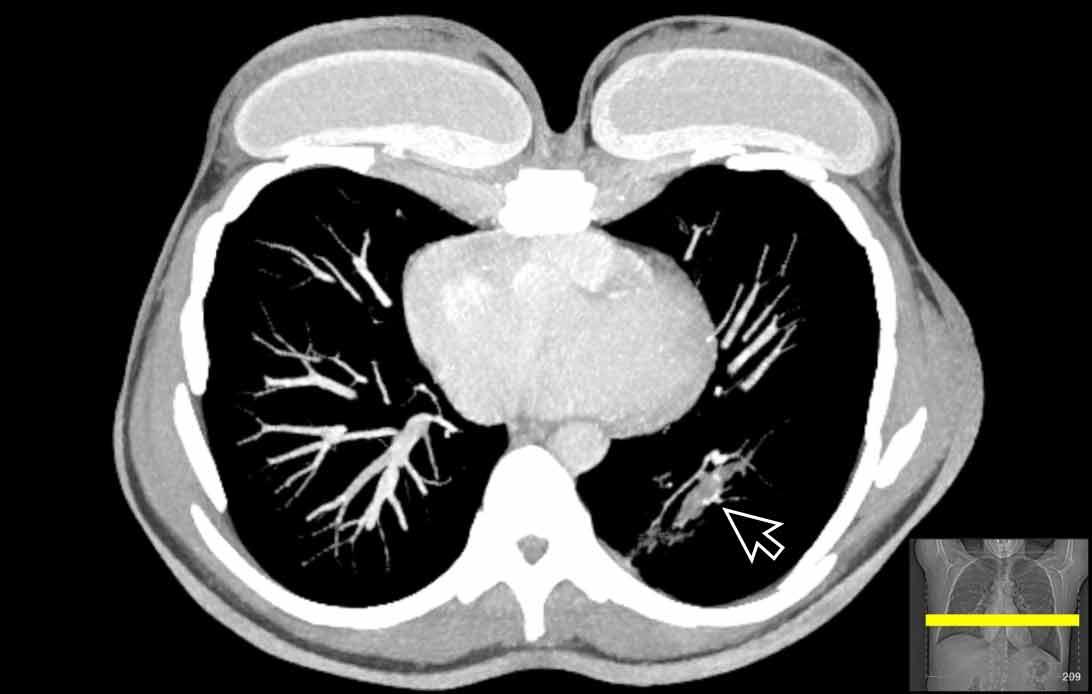

Hình ảnh

Cuộn qua các hình ảnh.

Theo dõi các phế quản của thùy dưới phổi trái cho thấy nhánh phân thùy đầu tiên của thùy dưới phổi trái còn thông; đó là phế quản phân thùy đỉnh.

Các ghim phẫu thuật nằm tại vị trí của các phân thùy đáy sau và đáy bên (LB9/10), vốn thường được cắt bỏ cùng nhau.

Do đó, phân thùy phổi có hình ảnh kính mờ và đông đặc phải là phân thùy đáy trước của thùy dưới phổi trái (LB8).

Động mạch phổi đến phân thùy này cũng không ngấm thuốc cản quang, và bản đồ tưới máu iốt nhấn mạnh thêm tình trạng nhồi máu.

Bệnh nhân đã được phẫu thuật lại và tiến hành cắt bỏ phân thùy bị nhồi máu, với xác nhận qua giải phẫu bệnh.

Tiếp tục với bản đồ tưới máu…

Trên bản đồ tưới máu iốt, có sự tưới máu ở thùy trên phổi trái và phân thùy đỉnh của thùy dưới phổi trái, nhưng không có sự tưới máu ở phân thùy đáy trước của thùy dưới phổi trái.